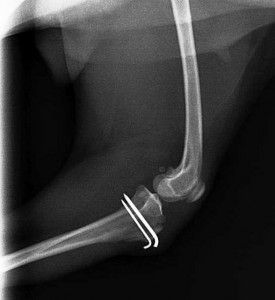

Fracturas

Es uno de los problemas más habituales en traumatología, las fracturas de huesos suelen ocurrir después de atropellos, caidas, disparos, golpes, etc.

La gran parte de la fracturas las resolvemos mediante la aplicación de fijación interna, y algunas con fijadores externos, dependiendo de las características de cada situación.

Las fracturas más frecuentes: mandíbula, húmero, cúbito y radio, cadera, fémur, tibia, metacarpianos.